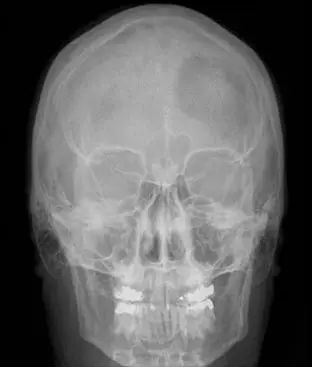

大多数脑膜瘤生长相对缓慢,具有良性肿瘤特征。国际卫生组织(WHO)将脑膜瘤分为三级。WHO I级脑膜瘤的复发风险相对较低,而更高等级脑膜瘤复发和侵袭性行为的可能性更高。WHO II级脑膜瘤为脊索状、透明细胞及非典型性病变,WHO III级脑膜瘤包括乳头状、横纹肌样和间变性肿瘤。WHO I级脑膜瘤是较常见的肿瘤,此类至少有九个亚型,较常见的是脑膜性、纤维性和过渡性脑膜瘤。下图显示的是一名61岁女性,头皮有一增大的肿块,CT扫描三维重建显示左额叶脑膜瘤累及骨质。这种影像学表现多提示肿瘤为一种侵袭性亚型。

患者前后位X线片显示左额叶透亮,表明该处脑膜瘤已经侵入骨质。(X线颅骨像很少作为初始诊断检查,其鉴别诊断范围相当广泛,包括骨肿瘤。)